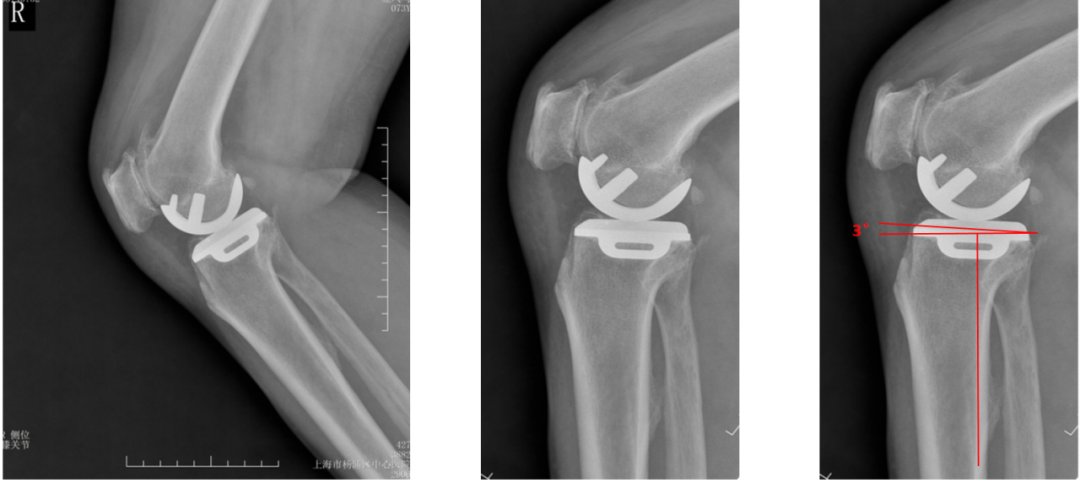

胫骨假体后倾角度(矢状位)

胫骨假体后倾角度:与胫骨侧位中轴线的垂线的最佳夹角 =7°。

胫骨假体后倾角度>7°

胫骨假体后倾角度:与胫骨侧位中轴线(后侧皮质)的垂线的夹角>7°。

胫骨假体后倾角度<7°

胫骨假体后倾角度:与胫骨侧位中轴线(后侧皮质)的垂线的夹角<7°。